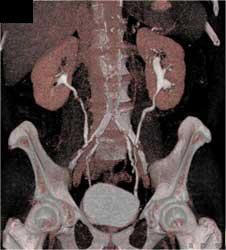

Normal CT Urogram